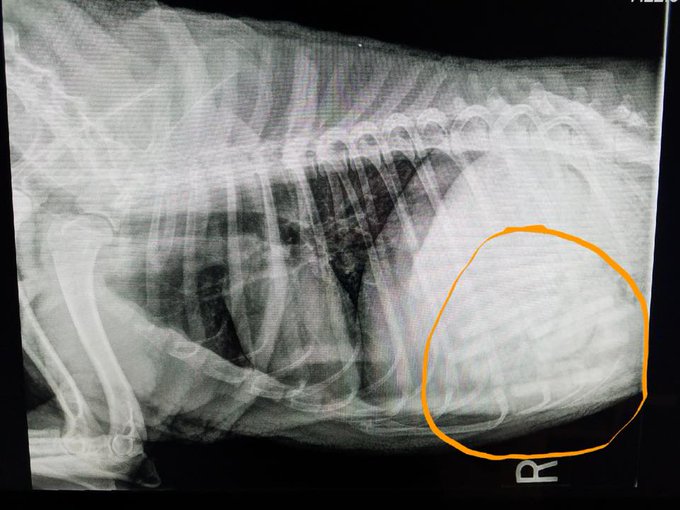

An Oklahoma vet removed 21 pacifiers from a dog’s stomach last week, according to local reports.